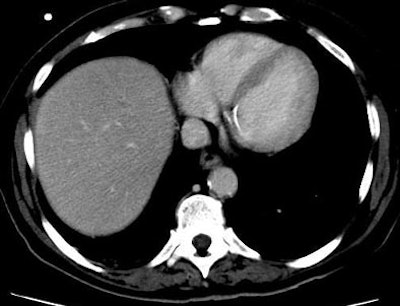

| Patient with fever after prolonged neutropenia. Above, arterial-phase CT of liver shows a type 2b lesion (arrow). Unenhanced CT (below) shows a corresponding hypoattenuating lesion, while portal-venous-phase CT (bottom) shows a tiny nonspecific hypodensity (type 1 lesion). This case demonstrates how arterial-phase CT adds specificity. Although portal-venous phase depicted the lesion, it would be extremely difficult to "call" it an abscess. The enhancement pattern on arterial phase CT makes for a more confident diagnosis. All images courtesy of Dr. Ur Metser. |

- Type I: hypoatteunating (Ia= sub-centimeter in diameter; Ib= at least 1 cm in diameter);

- Type II: hypoatteunating center with a hyperatteunating rim (IIa= thickness of hyperatteunating rim equal to or less than the radius of hypoatteunating center; IIb = thickness of hyperatteunating rim is greater than radius of hypoatteunating center);